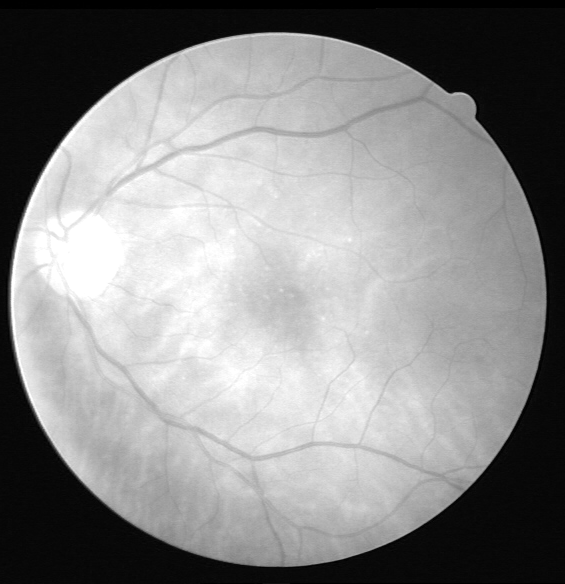

Refer to caption

(a) Original image

(b) Ground truth

(c) Binary mask

(d) Original image

(e) Ground truth

(f) Binary mask

Figure 8: Visual results for two sample STARE images.

Cross Validation

Cross-validation is used to assess the performance of the proposed model on ten images from the STARE dataset. STARE images are more challenging due to the inherent lower quality and poor contrast of these images. However, the proposed model achieves reasonable performance on the STARE dataset images. Typically, training is conducted on STARE images using leave-one-out validation to test the model’s validity. Very few works have provided cross-validation to evaluate the stability of the learned model on the STARE dataset. The average values 88.06/96.31 for Se/Sp are quite promising and demonstrate the significant performance of the proposed model. The average AUC value is 97.57% that reflects the generalization of the proposed model on a completely unseen STARE dataset to demonstrate its generalization capability. Therefore, we, believe that our proposed methodology can be reliably applied for automatic retinal vessel segmentation of the clinical applications, such as a computer-aided diagnosis pipeline or automated vascular quantification or localization. Figure 8 depicts the visual outcomes for 2 sample images from the STARE dataset. As evident from a visual comparison of ground truth and output segmentation masks, thick vessels are detected quite accurately, especially near the fovea region. Similarly, thin vessel pixels at the branches are also segmented with reasonable visual match.